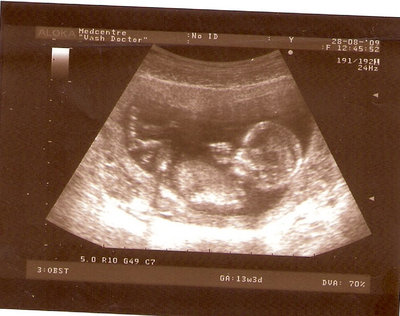

СЫН

| Вложения: |

2.jpg [ 110.14 КБ | Просмотров: 2625 ]

13 НЕД И 5 ДНЕЙ

3.jpg [ 96.81 КБ | Просмотров: 2623 ]

Nikisa писал(а): Foto prosto chudesnoe. A na kakom sroke uznali, chto sin.............. НА 13 НЕДЕЛЯХ.КАК РАЗ ВОТ В ЭТО узи, ОНО УМЕНЯ ВТОРОЕ БЫЛО. ЭТО КОНЕЧНО МАЛЕНЬКИЙ СРОК ДЛЯ ОПРЕДЕЛЕНИЯ ПОЛА. НО Я ПОПРОСИЛА ВРАЧА(ЭТО КТСТАТИВ РОССИИ БЫЛО) ХОТЯ БЫ ПРЕДПОЛОЖИТЬ. ЕЙ ВСЁ ТАКИ УДАЛОСЬ РАССМОТРЕТЬ.НУ ВООБЩЕМ ЧЕРЕЗ НЕСКОЛЬ ДНЕЙ ПОЙДУ К ВРАЧУ, УЖЕ АМЕРЕКАНСКОМУ И УЗНАЮ ТОЧНО. К ТОМУ ВРЕМЕНИ У МЕНЯ БУДЕТ СРОК 18 НЕДЕЛЬ. ХОТЕЛОСЬ БЫ ПОСМОТРЕТЬ НА ДРУГИЕ ФОТО НА ЭТОМ СРОКЕ ИЛИ БОЛЬШЕ. ТАК ЧТО ВЫКЛАДЫВАЙТЕ, ЕСЛИ НЕ ЖАЛКО!